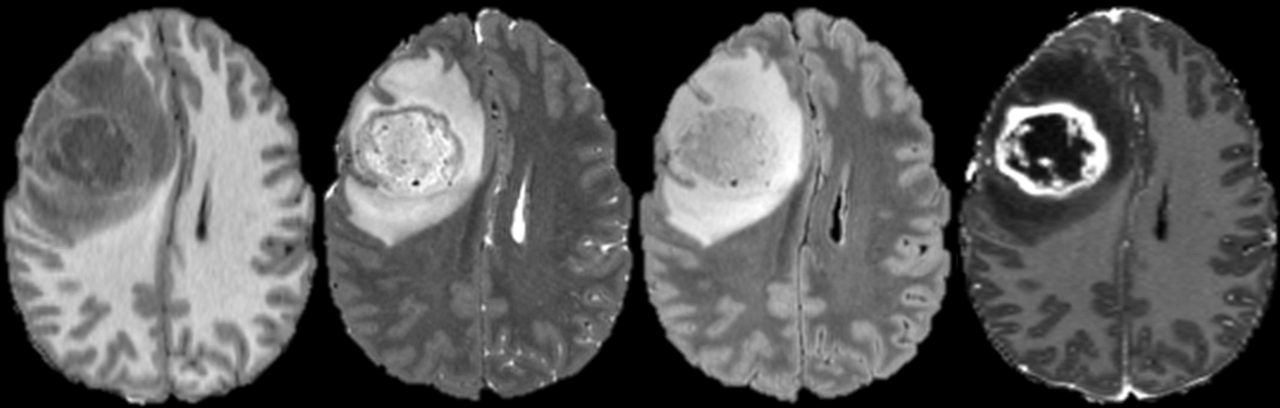

Axial MR images of glioblastomas from 8 different patients with IDH mutant (AD) and chromosome 7/10 aneuploid tumors (EH). T2-weighted FLAIR images (left) are shown beside corresponding T1-weighted postcontrast images (right). Relative probabilities of IDH mutation (Prob. IDH) and chromosome 7/10 aneuploidy (Prob. 7/10) generated from artificial intelligence models are shown for image set of images.